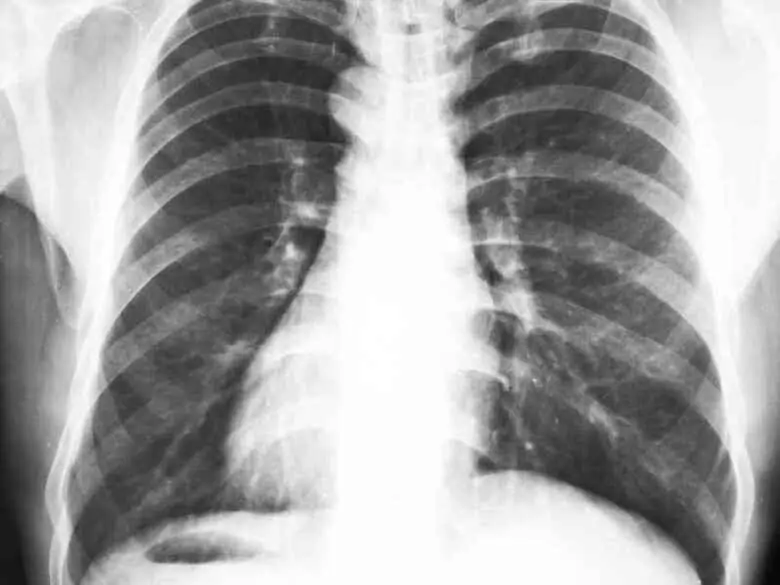

Aller à : Symptômes et évolution Quand consulter Traitement Publicité: Symptômes et évolution douleur thoracique d'origine cardiaque Quand consulter et traiter la douleur thoracique d'origine cardiaque Traitement douleur thoracique d'origine cardiaque.